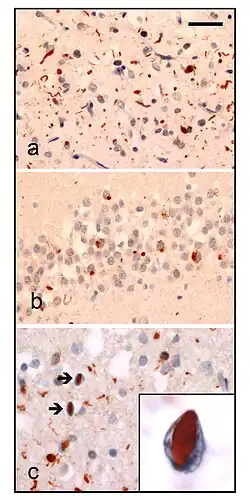

| Neuropathologic analysis of brain tissue from FTLD-TDP patients. Ubiquitin immunohistochemistry in cases of familial FTLD-TDP demonstrates staining of (a) neurites and neuronal cytoplasmic inclusions in the superficial cerebral neocortex, (b) neuronal cytoplasmic inclusions in hippocampal dentate granule cells, and (c) neuronal intranuclear inclusions in the cerebral neocortex (arrows). Scale bar; (a) and (b) 40 μm, (c) 25 μm, insert 6 μm. | |